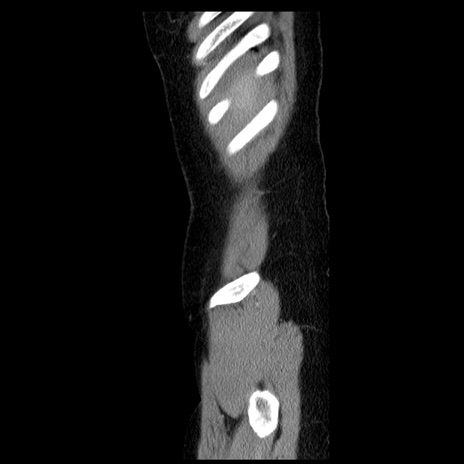

横断像